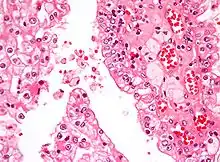

| Micrograph showing the most common type of kidney cancer (clear cell renal cell carcinoma). H&E stain. | |

The most common type of kidney malignancy is renal cell carcinoma,[33] which is thought to originate from cells in the proximal convoluted tubule of the nephron.[15][34] Another type of kidney cancer although less common, is transitional cell cancer (TCC) or urothelial carcinoma of the renal pelvis.[35] The renal pelvis is the part of the kidney that collects urine and drains it into a tube called the ureter.[35] The cells that line the renal pelvis are called transitional cells, and are also sometimes called urothelial cells. The transitional/urothelial cells in the renal pelvis are the same type of cells that line the ureter and bladder. For this reason TCC of the renal pelvis is distinct from RCC and is thought to behave more like bladder cancer.[35] Other rare types of kidney cancers that can arise from the urothelial cells of the renal pelvis are squamous cell carcinoma and adenocarcinoma.[15]

Renal cell carcinoma has been further divided into sub-types based on histological features and genetic abnormalities. The 2004 WHO Classification of the Renal Tumors of the Adults describes these categories:[39]

- Clear cell RCC